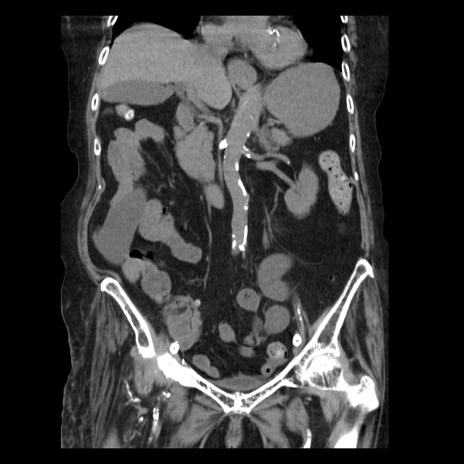

症例14(冠状断像)

【症例】 90歳代女性

【主訴】 腹痛・嘔吐

【現病歴】今朝から左側腹部痛を認めた。 経過観察していたが、嘔吐を認めたため来院。

【既往歴】 子宮癌術後

【身体所見】 意識清明、BP 127/54mmHg、P 98bpm Sp02 95%(RA)、BT 35.8°C、腹部平坦・軟腸ぜん動音聴取良好、右下腹部圧痛(+) 反跳痛なし

【データ】WBC 9800、CRP 0.46